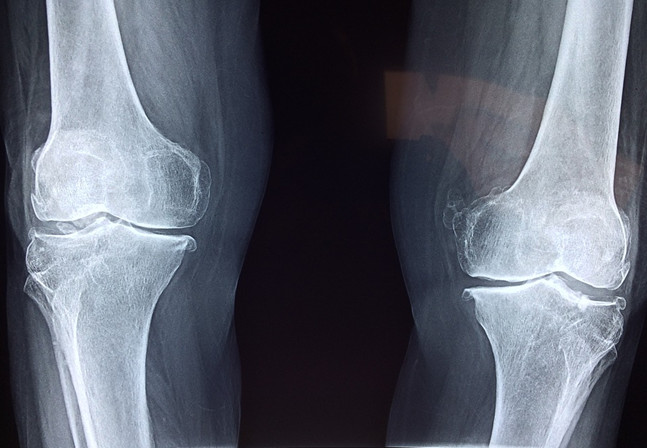

氨糖的全稱是氨基葡萄糖,本質(zhì)上是一種氨基己糖,能夠參與構(gòu)造人體組織和細(xì)胞膜,尤其是對(duì)合成、修復(fù)關(guān)節(jié)軟骨以及關(guān)節(jié)滑液分子的中間物有重要的作用。當(dāng)關(guān)節(jié)軟骨吸收到足夠的氨糖時(shí),軟骨本身就會(huì)變得更強(qiáng)健飽滿,可以在關(guān)節(jié)中牢牢包裹住人體活動(dòng)的硬質(zhì)骨骼,確?;顒?dòng)硬骨在完成相應(yīng)的肢體動(dòng)作時(shí)不與相鄰的骨骼發(fā)生碰撞,并且骨骼之間的接觸面也因?yàn)橛辛孙枬M的軟骨,產(chǎn)生的摩擦并不會(huì)傷害到硬骨本身。

相反,如果身體當(dāng)中缺少氨糖補(bǔ)給的軟骨會(huì)怎么樣呢?在骨骼的摩擦中,原本飽滿健康的軟骨會(huì)被磨損,漸漸地保護(hù)骨骼的作用就會(huì)減弱,失去保護(hù)緩沖的動(dòng)作在完成肢體動(dòng)作時(shí)相互碰撞生痛,也就是許多中老年人遇到腿腳不便的情況了。

為什么是中老年人會(huì)遇到這樣的情況呢?事實(shí)上人體是能夠自身合成氨糖的,這保證了人體在幼年和青壯年時(shí)期的骨骼關(guān)節(jié)不會(huì)出現(xiàn)疼痛不便的現(xiàn)象,可隨著年紀(jì)增長(zhǎng),身體合成氨糖的速度和數(shù)量隨之減少了,也就開(kāi)始需要人自行從外界去補(bǔ)充氨糖才能保持關(guān)節(jié)的靈敏舒適。